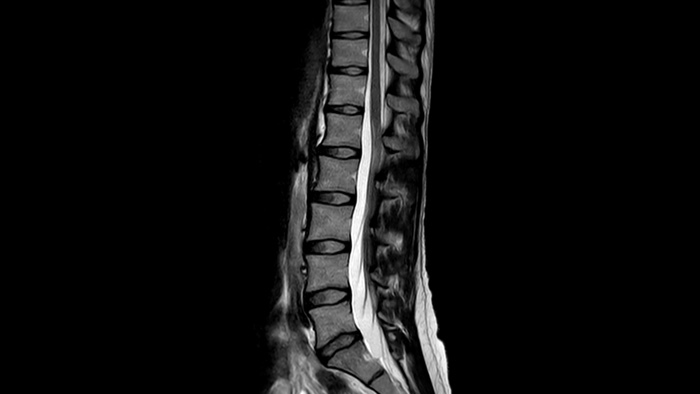

SmartSpeed AI enables to decrease the scan time up to 65% with equal or better image quality

Speed & Comfort

Provide up to 40% reduction in breath holds, with virtually equal image quality4.